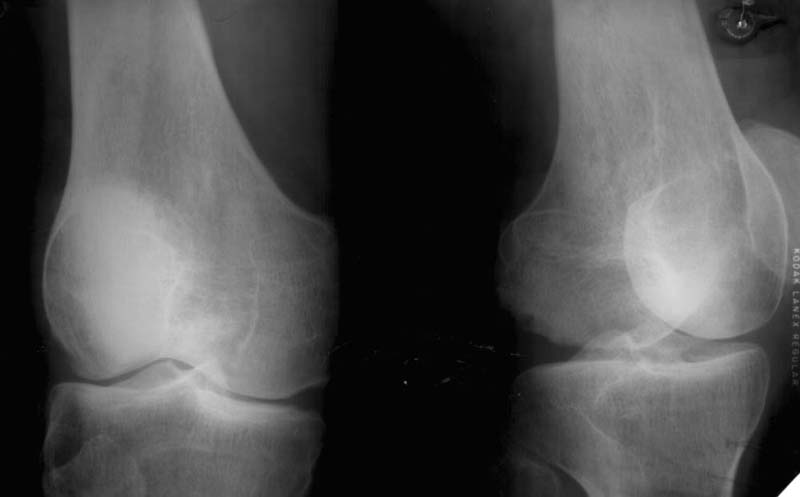

At the present time a post traumatic defect of lateral femoral condyle is observed. On the X-rays of left knee, a lateral femoral condyle defect is observed up to the 1/3 of the joint surface. Clinical examination of left knee joint revealed moderate atrophy of the muscles of left femur and shin, moderate pain with palpation of the lateral joint line, pathological deviation of the shin to the outside up to 20 degrees at doing the clinical tests, accompanied by the appearance of moderate pain, motions in the knee joint are slightly restricted.